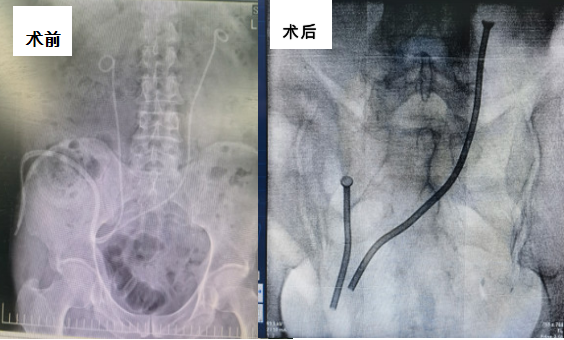

首例永久性输尿管金属支架植入术。

张军晖主任在术前充分评估,针对术中可能出现的各种情况充分论证、准备,在确保万无一失的情况下于2月19日开展手术。由于患者既往行膀胱癌根治术,吻合口位置特殊,情况复杂,术中反复调试,不断修正,直至确保金属支架能完全覆盖狭窄全段,术后不会发生再狭窄可能。在两位专家的通力合作下手术顺利完成,金属支架位置良好。患者术后引流良好,未出现任何不良反应。